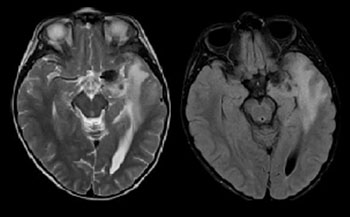

МРТ исследования головного мозга и DSC-перфузия. В области левого кавернозного синуса экстрааксиальное образование, с широким прилежанием к ТМО, окруженное перифокальным отеком и масс-эффектом на медиальные отделы височной доли левого полушария головного мозга. При анализе Т2 и Т2flair изображений, визуализируется особенный симптом «Инь-Ян», характеризующийся наличием двух компонентов у опухоли, один из которых гипоинтенсивный (гипоклеточная часть, представленная коллагеновой стромой), а другой гиперинтенсивный (гиперклеточная часть) по отношению к мозговой паренхиме. Кроме того данное образование демонстрирует гомогенное, относительно однородное накопление парамагнетика на постконтрастных изображениях, а так же наличие диспластически расширенных сосудов опухоли на SWI последовательностях, что отчетливо подтверждается высоким кровоснабжением данной опухоли на перфузионных картах с высокими значениями rCBV. Бесконтрастная Кт – демонстрирует неоднородную опухоль с наличием в структуре кальцинатов.⠀В настоящее время нет никаких патогномоничных признаков в диагностике данной опухоли, но симптом «Инь-ян» и выраженное гетерогенное контрастирование могут внести определенный вклад в диагностике данного образования.⠀Солитарная фиброзная опухоль (послеоперационный микропрепарат), окраска гематоксилином и эозином, увеличение х10. а – гипоклеточная зона образования, представленная прослойками коллагена (черные стрелки). б – гиперклеточная зона (красные стрелки), а так же наличие тонкостенных диспластично расширенных ветвящихся сосудов по типу «рогов оленя» ("staghorn" sign)